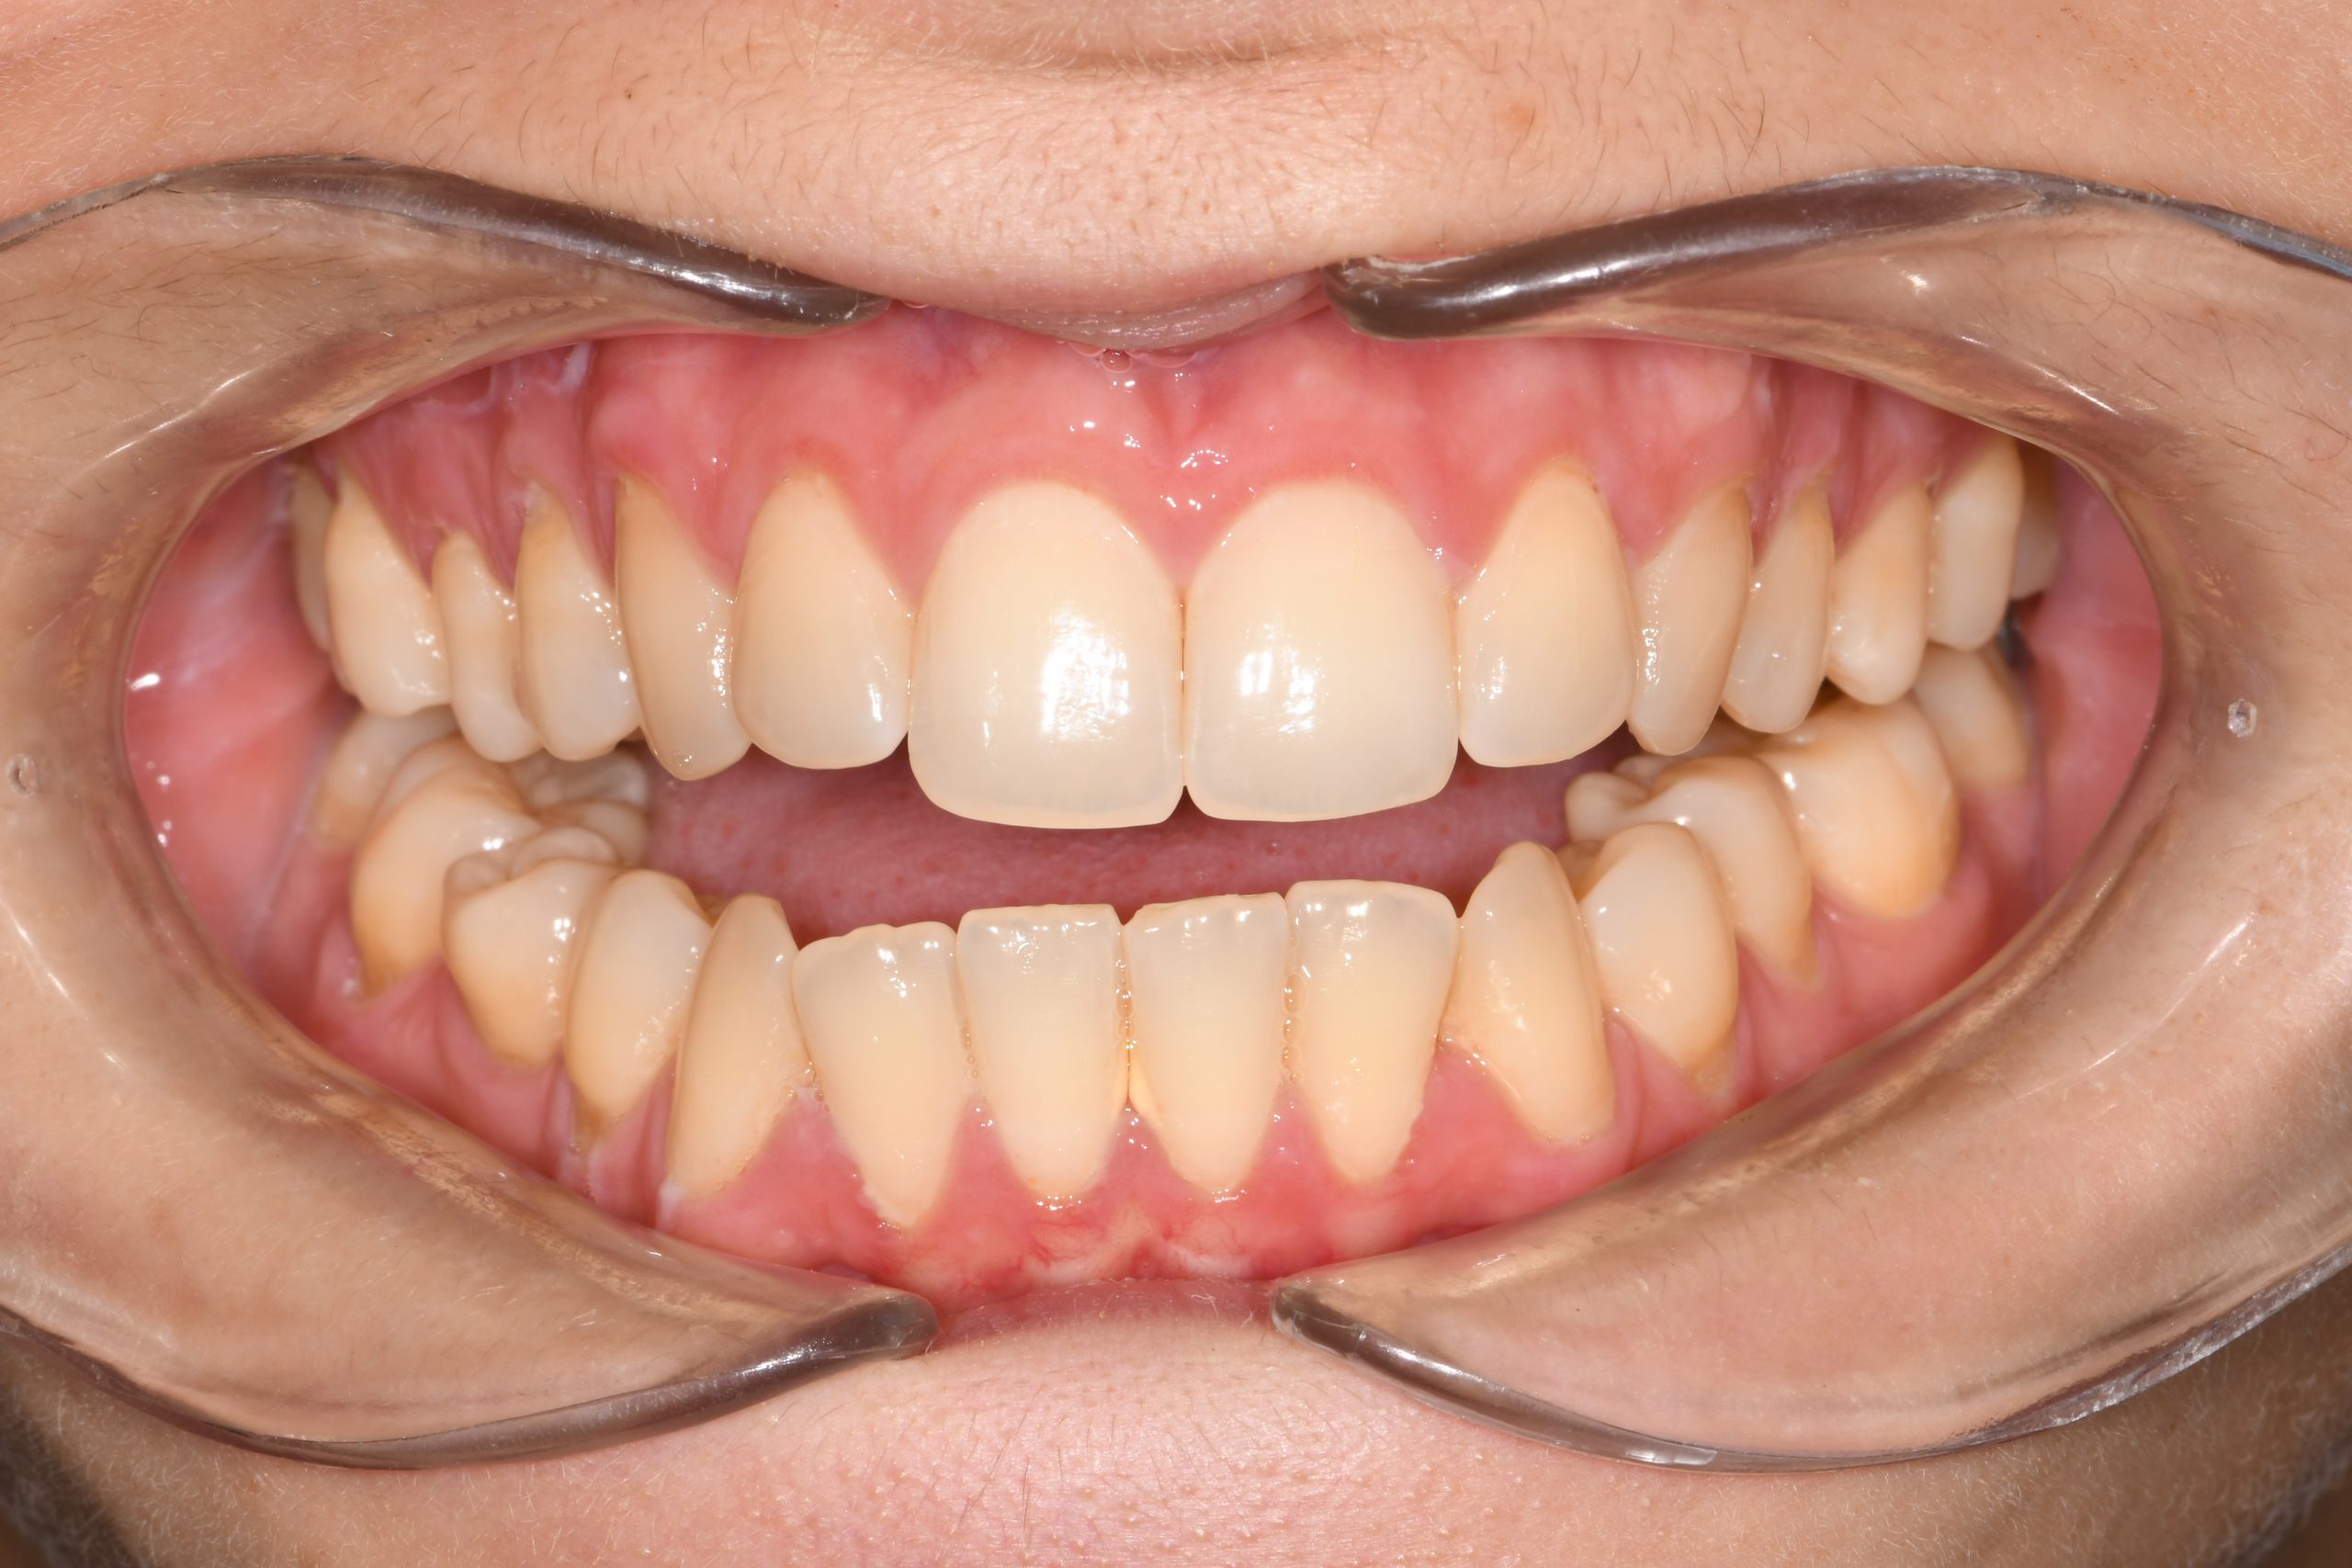

Az elmúlt évekből rengeteg szakmai referenciát tudnánk bemutatni, amelyek különböző fogszabályozási problémákat oldottak meg. Válogatva a több száz esetből, ezen az oldalon olyan képeket, információkat igyekeztünk bemutatni, amelyeknek a segítségével a jövőbeni pácienseinknek azt tudjuk üzenni: A Te fogsorod is lehet gyönyörű!

(Képeket a Pácienseink külön írásos beleegyezésével mutatjuk be!)